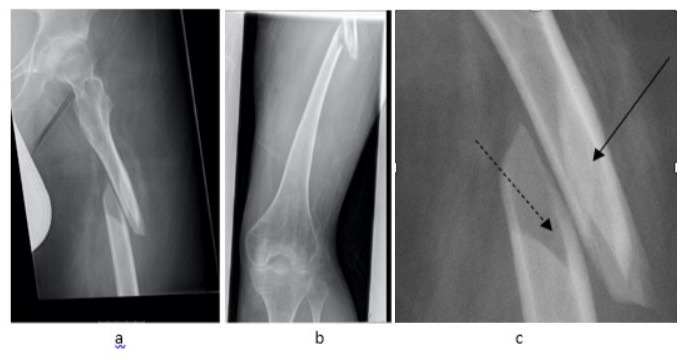

We report of a 21-year-old male patient with a body weight of 53.2 kilograms who slid of his toilet chair hearing a crack in his left femur. The patient was sitting in a wheelchair for about 8 hours a day and studying at university. He was diagnosed a proximal femoral shaft fracture (AO/OTA 32 B3.1) in our emergency department (Figure 1a,b). The femoral shaft diameter was 10.2mm, the medullary canal 9.0mm. Due to the relevant dislocation of the fracture fragments, the shortening of the upper leg, the poor fracture localization for splinting and the massive pain, we saw an indication for urgent operative stabilization and the patient was immediately transferred to our OR. Despite the tiny intramedullary canal, we aimed for the highest possible stability to enable wheelchair transfer and the ability to sit for several hours. Due to the wedge fragments, flexible nailing of the fracture seemed not to be an adequate stabilization. The available rigid femoral nails had diameters of minimum 9.0mm. Considering the poor bone quality and thin cortical is, reaming of the medullary canal was not an option. As proximal humerus nails were used in femoral shaft fractures in children and adolescents before [6,7] we decided upon an 8.2mmx300mm T2 Proximal Humerus Nail (Stryker Howmedica, Mahwah, USA).

Figure 1a, b: Proximal femur fracture AO 32 B3.1 (composed X-ray, Figure. 1a). The detail view (Figure. 1b) depicts the displaced (solid line) and none displaced (broken line) wedge fragments.